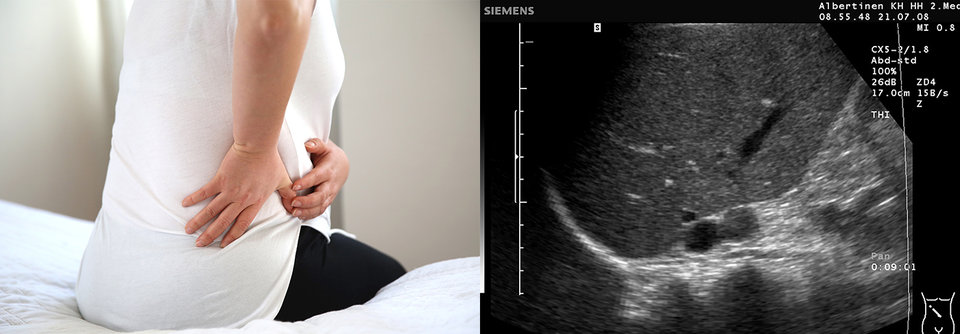

Zufallsbefund Nebennierenvergrößerung. Ob der  Tumor Hormone im Übermaß produziert, lässt sich allein anhand einer Ultraschalluntersuchung nicht sagen. Zufallsbefund Nebennierenvergrößerung. Ob der Tumor Hormone im Übermaß produziert, lässt sich allein anhand einer Ultraschalluntersuchung nicht sagen. © iStock/Handemandaci; Immanuel Albertinen Diakonie/sonographiebilder.de

Entdeckt man bei der Bildgebung unerwartet eine Raumforderung in der Nebenniere, sollte diese schnell abgeklärt werden. Ist das Inzidentalom maligne, muss man mit einem aggressiven Wachstum rechnen.